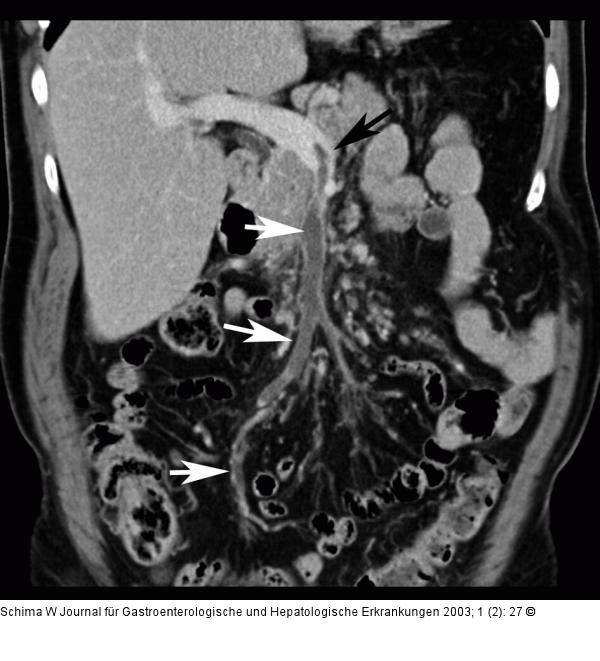

Abbildung 1: Mesenterialvenenthrombose